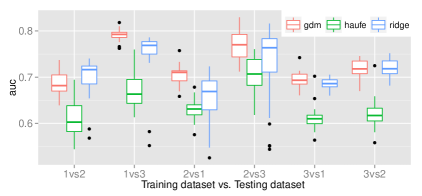

Multi-site study

To assess the predictive performance of the compared methods in a multi-site setting, we used the Schizophrenia dataset that comprises data from three sites. All models had their respective parameters cross-validated while training in one site before making predictions in the other two sites. Each training involved using of the site samples to allow for resampling the training sets 100 times to yield a distribution. The reproducibility across the resampled sets was measured using the inner product between model parameters. The multi-site prediction and reproducibility results are visualized in figure 3.

In five out of six cross-site prediction settings, GDM outperformed all compared methods in terms accuracy. Also, GDM had higher reproducibility than ridge regression, while having slightly lower reproducibility than the generative procedure in Haufe et al. (2014).